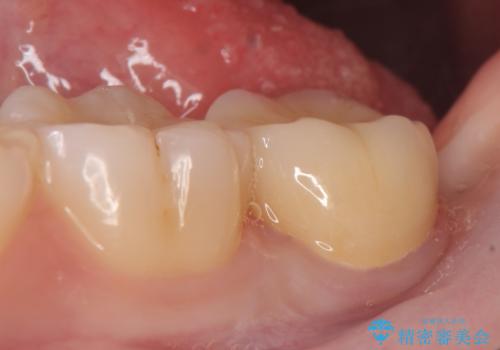

- 左下7の銀歯を白くしたいといらっしゃった方の症例です。

左下7遠心(下記のX線写真の左側)の歯質が歯肉縁下でかつポケットも深かったため、歯茎を下げる歯周外科を行いました。

その後歯茎の治りを待ちポケットが正常値であることを確認後、オールセラミッククラウンによる補綴を行いました。